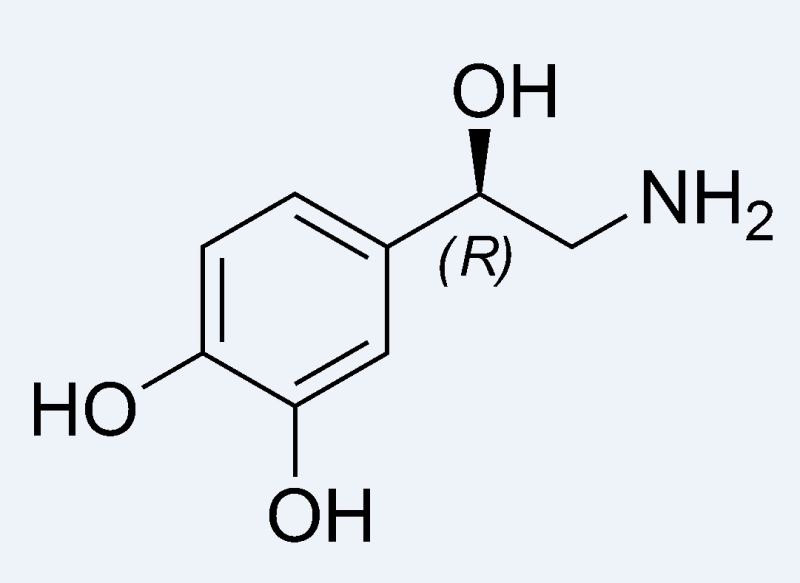

şu gördüğünüz adrenalin ve yine aynı halkasal yapıyı görüyorsunuz

bu da noradrenalin, yine halkasal yapıya dikkat ediniz.